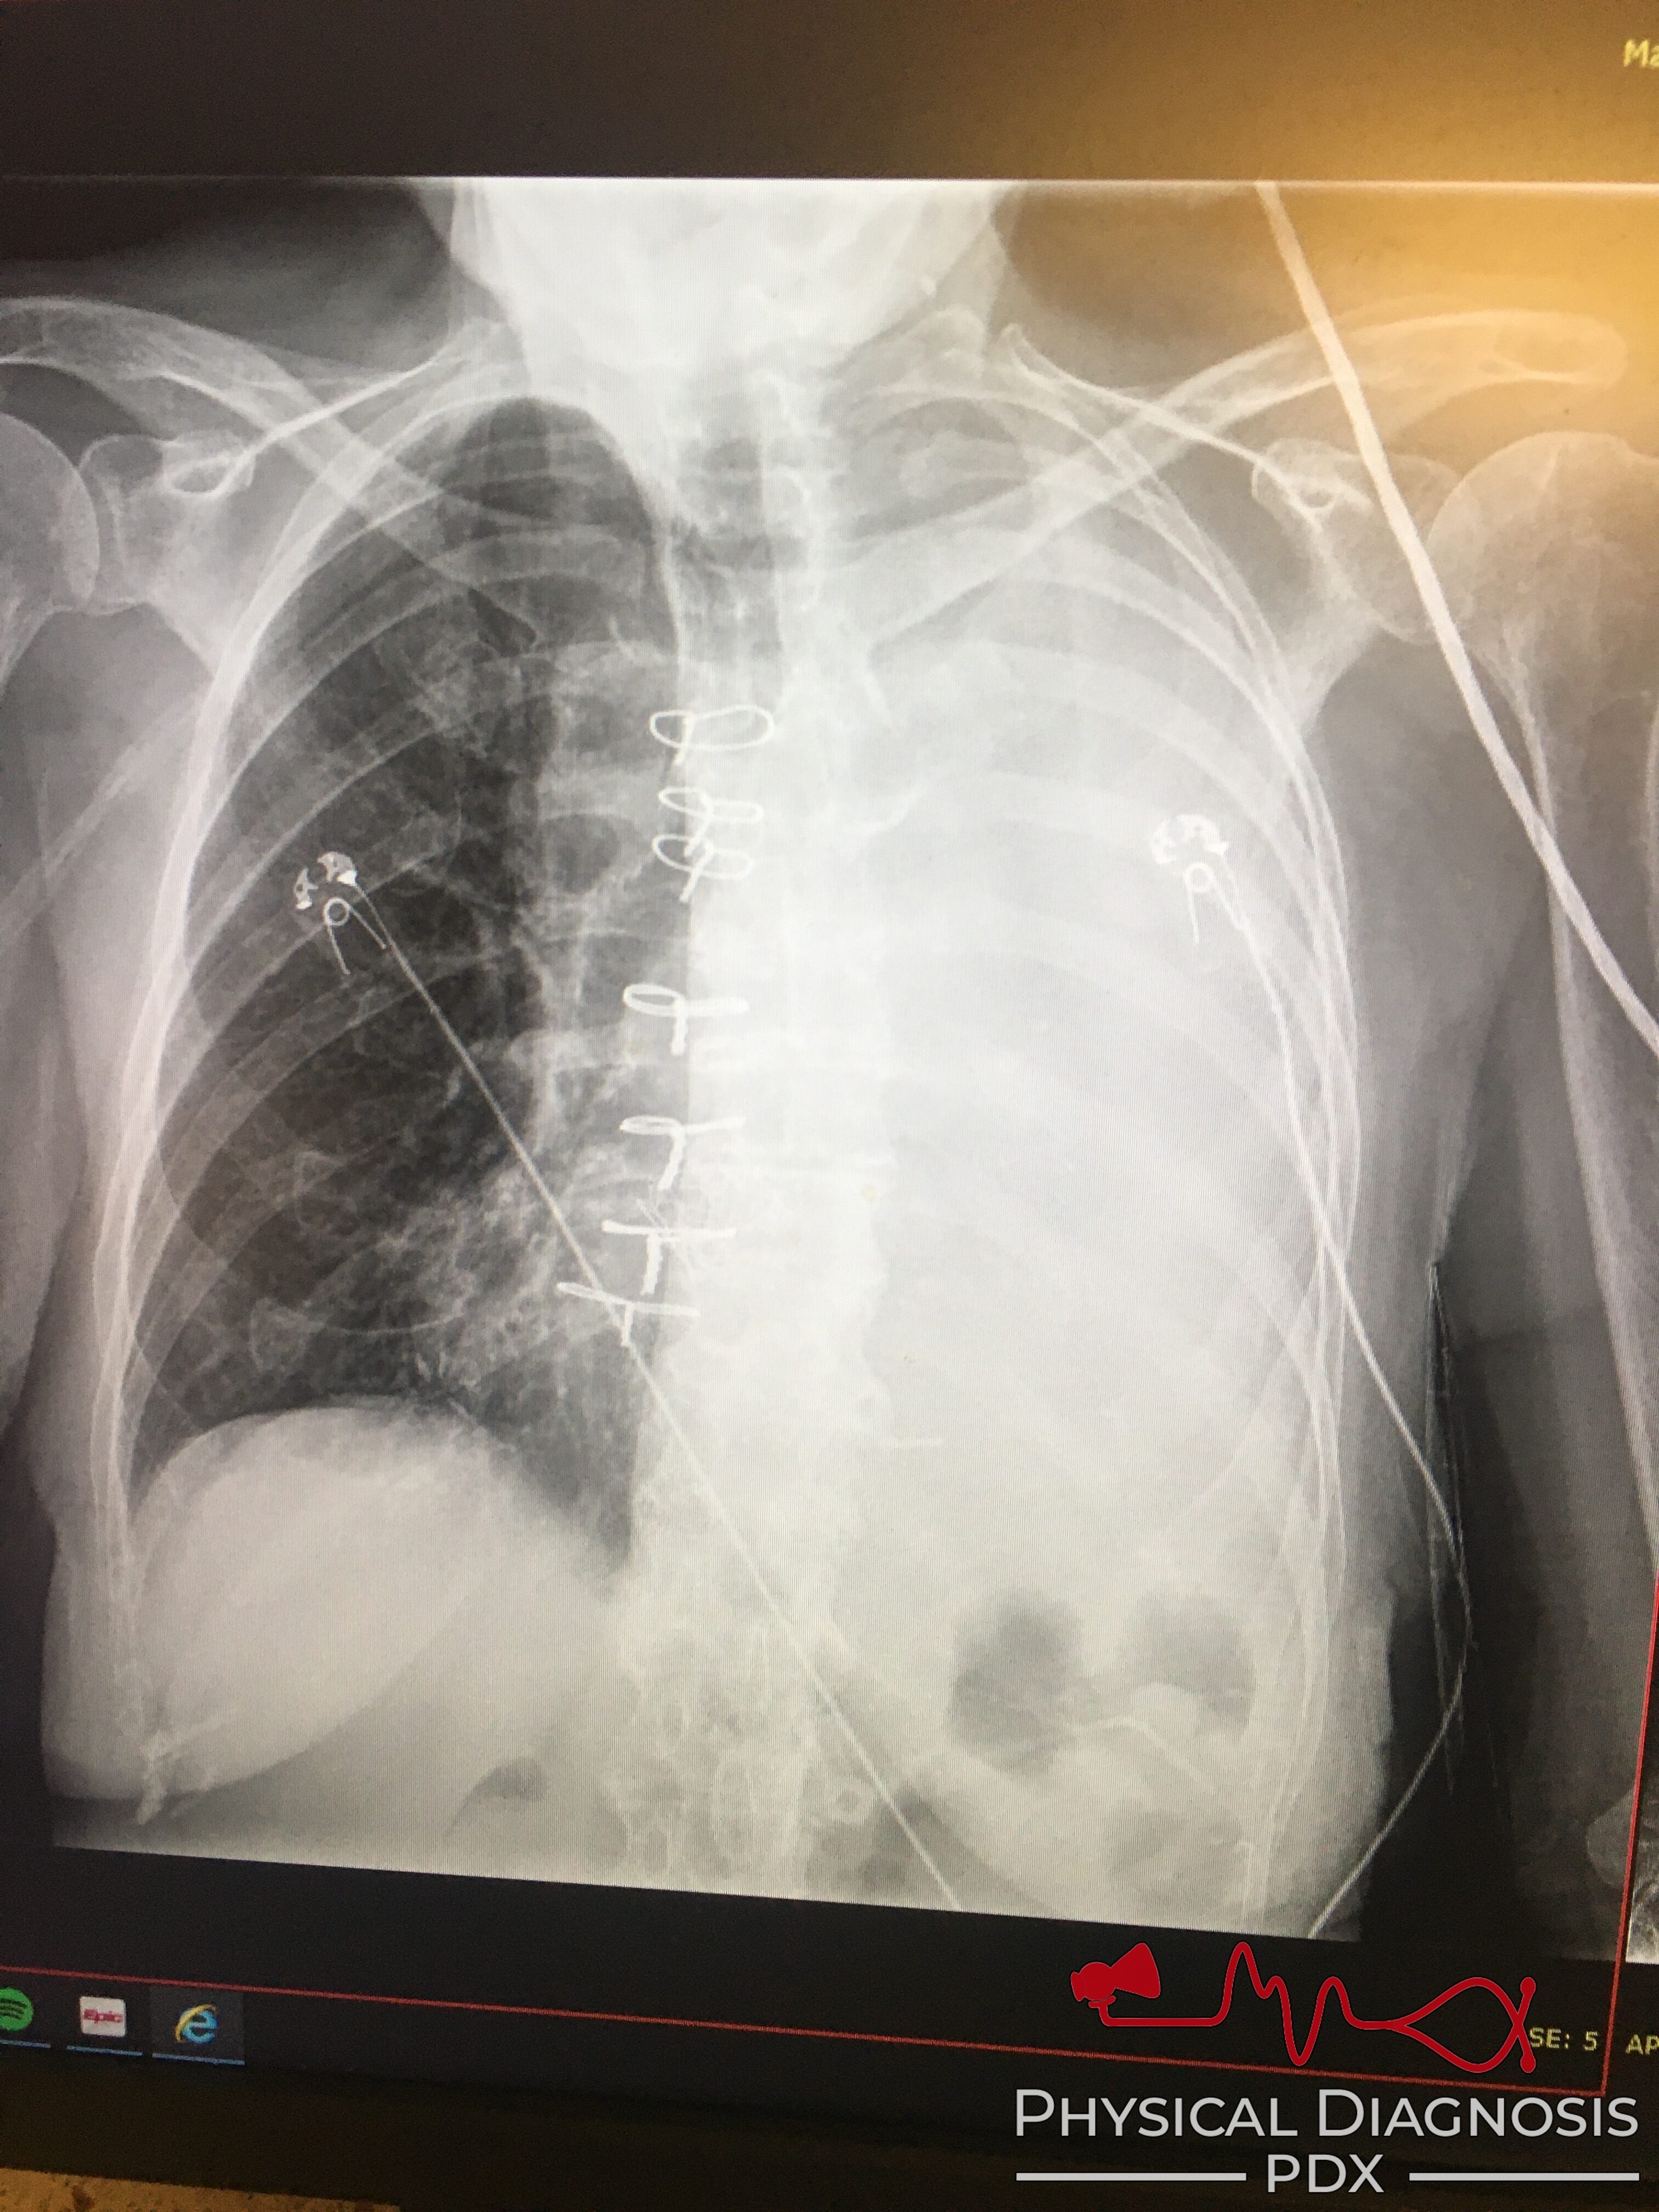

Patient 1:

This patient is a middle aged woman who presented with chronic cough. The finding is asymmetric chest expansion on inspiration. Her CXR shows a complete white out of her left lung. She had a large, malignant pleural effusion from a small cell lung cancer.